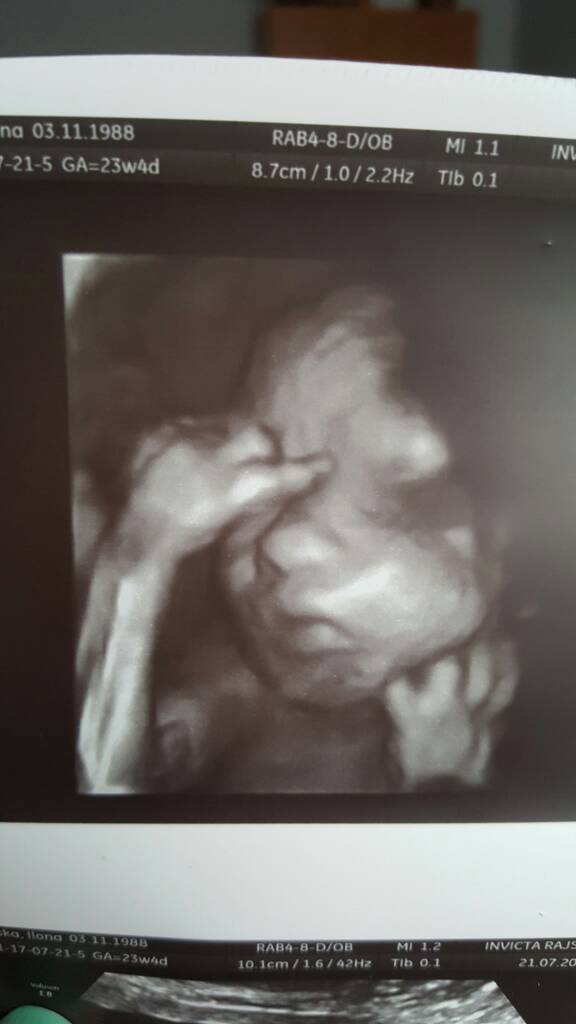

Miałam dziś też badania przepływów i zbadany został malutki tak jak na połówkowym

Tak nam ładnie się pokazał[emoji7]

1500639448-aaaaaa.jpeg

Jestem taka szczęśliwa [emoji16]Tylko portfel pusty [emoji23]i gdzie tu myśleć o wyprawce [emoji28]ale najważniejsze że wszystko jest ok [emoji1]